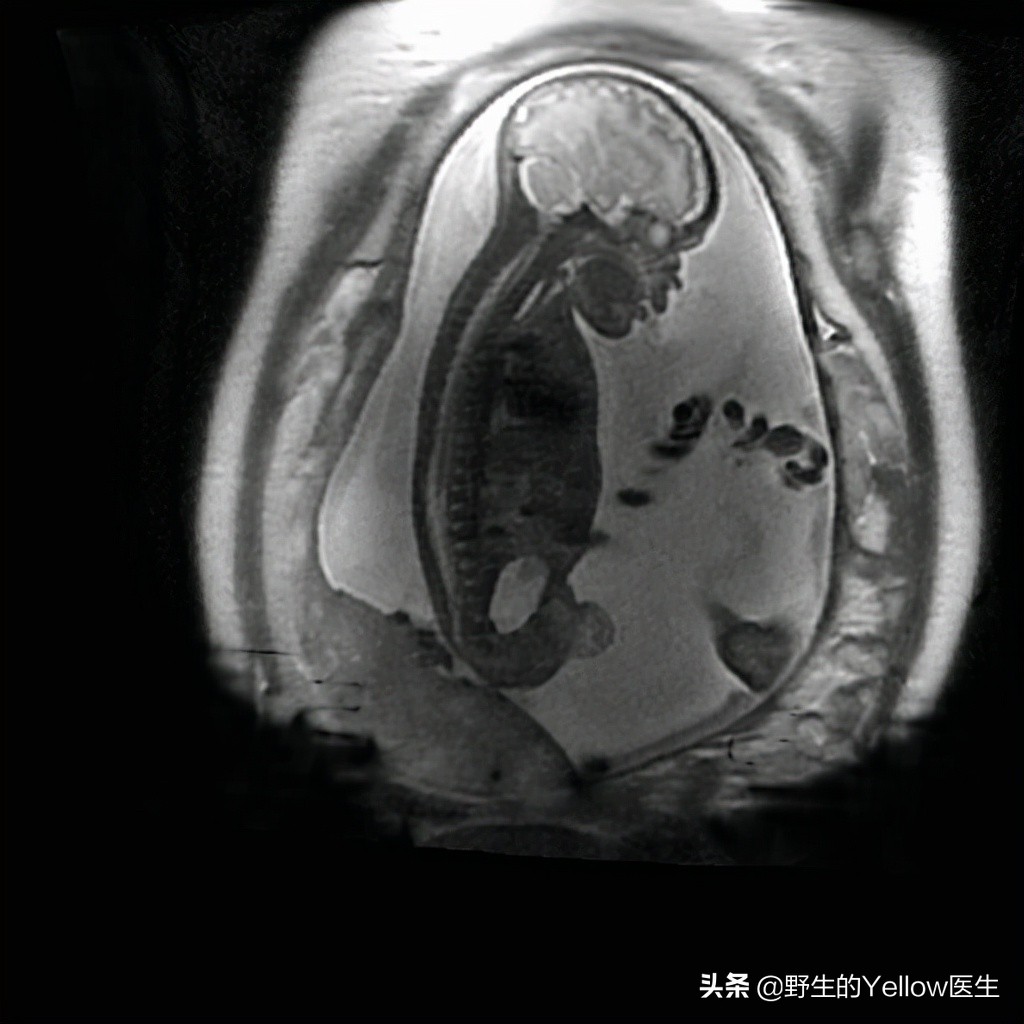

像下图所示的 胎儿磁共振 ,通常都需要20分钟以上,如果胎动频繁可能还需要几十分钟,甚至改期分次扫描,以获得满意图像。

胎儿磁共振